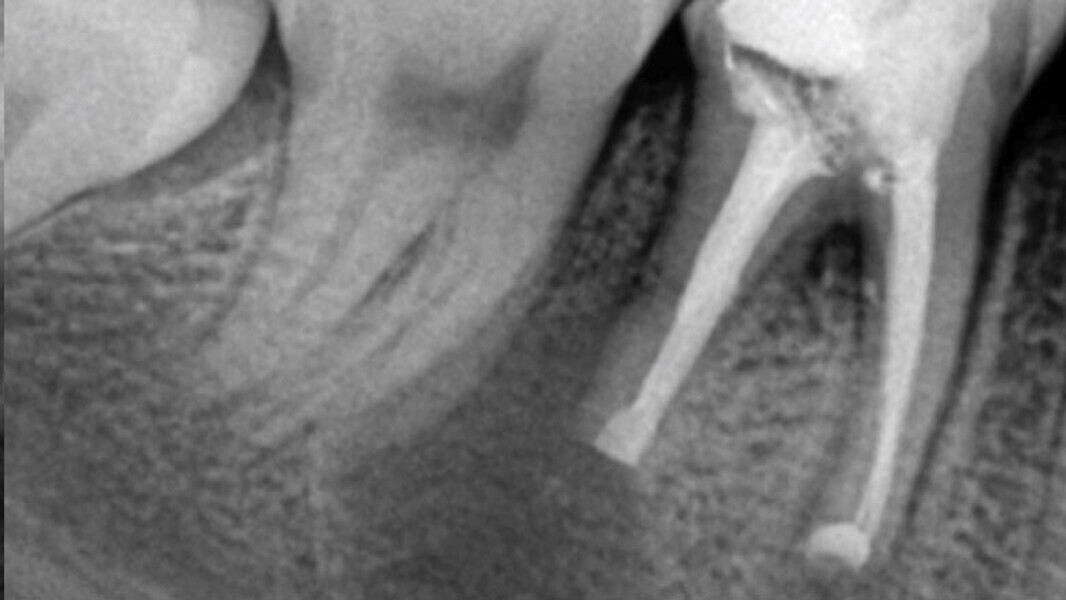

Figura 1. Inclinación de la raíz distal del primer molar inferior derecho hacia lingual. Ubicada aproximadamente a 10 mm de la cortical ósea vestibular, lo que hace imposible hacer el abordaje quirúrgico a través de microcirugía.